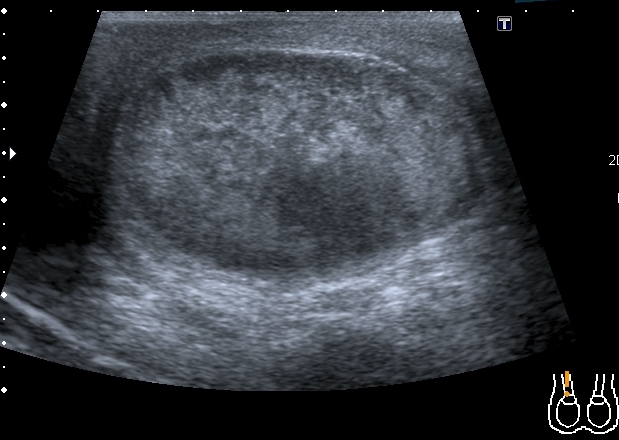

Сегодня смотрел его на контрольном УЗИ: в правой половине мошонки - небольшое количество жидкости. Яичко прежних размеров, кровоток в яичке востановился, но определяется в основном в подоболочечной зонеВ области ворот яичка - гипоэхогенный участок с нечёткими контурами. Вопрос: что делать дальше

Пациент выписался домой, пока на контроль не появлялся. Через три дня после операции кровоток в яичке был достаточно "живой", нерестриктивный (см. скан с триплексом), но большое сомнение оставил приличный по размерам гипоэхогенный участок. Да и анамнез - около двух дней без кровотока... Во время операции хирурги делали пробу - надсекали оболочку яичка - получили капилярное кровотечение, на основании чего заключили, что яичко жизнеспособно. Я про такую методу , честно говоря, не слышал, дай Бог, чтоб эта проба работала.Dr Alex писал(а):Интересно, "ожило" ли яичко?